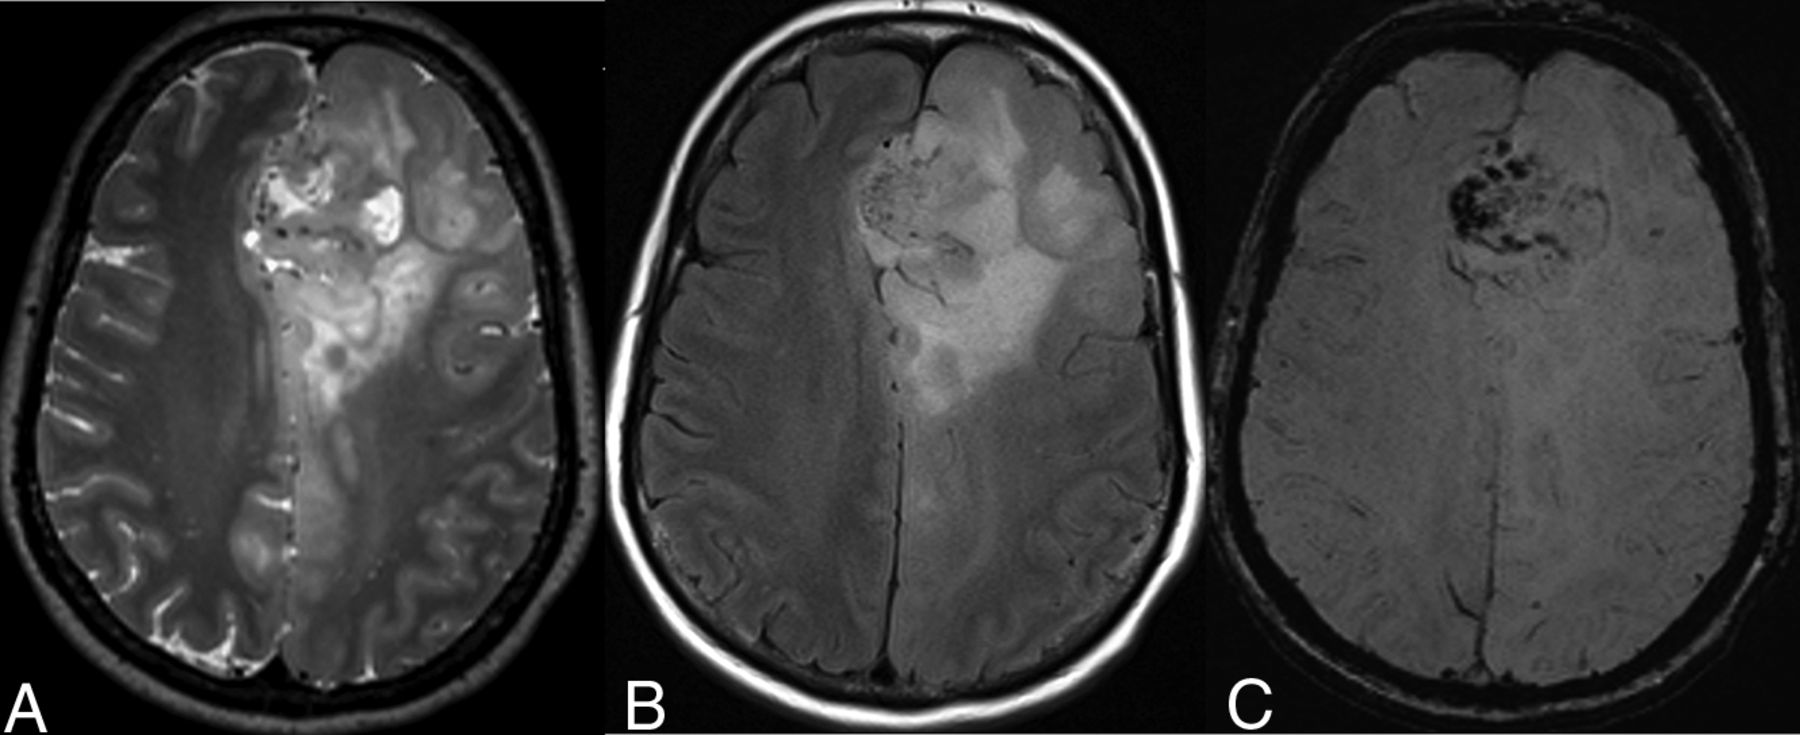

A 38-year-old man with a left frontal lobe diffuse astrocytoma, IDH-mutant and 1p/19q-noncodeleted, showing characteristic imaging features. A, On T2WI, the mass is homogeneously hyperintense, sharply marginated, and without significant cortical infiltration. B, FLAIR sequence shows central suppression of signal compared with the T2WI, except for a peripheral rim (ie, T2-FLAIR mismatch sign). C, T2*WI shows lack of susceptibility blooming.

Two neuroradiologists, with 5 and 13 years of experience, blinded to the 1p/19q-codeletion status, analyzed the MR images from the training dataset in consensus. They measured 14 neuroimaging metrics: 1) primary lobe: yes/no centered on frontal lobe; 2) texture: more or less than 75% of the tumor showing homogeneous signal intensity on T1WI/T2WI; 3) margins: more or less than 75% of the tumor showing sharp/circumscribed margins; 4) T2-FLAIR mismatch sign: the presence or absence of complete/near-complete hyperintense signal on T2WI and relatively hypointense signal on FLAIR except for a hyperintense peripheral rim19; 5) T2* susceptibility blooming: present or absent; 6) contrast enhancement: present or absent; 7) cysts: present or absent; 8) necrosis: present or absent; 9) maximum tumor diameter (centimeter); 10) cortical infiltration: present or absent; 11) peritumoral edema: present or absent; 12) gliomatosis: yes/no involvement of ≥3 lobes; 13) midline shift (centimeter); and 14) hydrocephalus: present or absent. Figures 1 and 2 show the characteristic imaging appearance of IDHmut-Noncodel and IDHmut-Codel LGGs, respectively, including a description of several of the above imaging metrics. Univariate and multivariate logistic regression analysis of the MR imaging characteristics and patient age for predicting the 1p/19q-codeletion status was undertaken. On the basis of these results, a classification algorithm for 1p/19q prediction was developed.